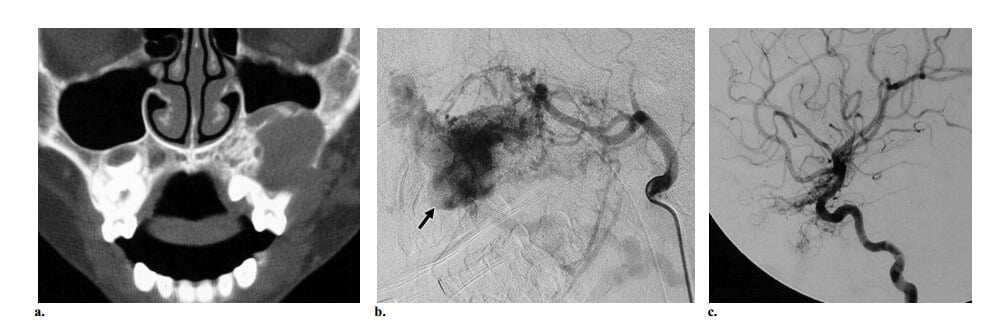

Hình 5: CAMS kiểu 2 ở bé gái 10 tuổi có bệnh sử 1 năm liệt nửa người tiến triển. Ghi nhận phù kết mạc và lồi mắt trái. (a, b) Axial CT ở mức hốc mắt (a) và não (b) thấy tổn thương mạch máu bắt quang ở hạch nền trái. Tổn thương gây hiệu ứng choán chỗ ở não thất bên trái. Ngoài ra, thấy các cấu trúc ngoằn ngoèo xung quanh thần kinh thị. (c) Chụp động mạch cảnh trong thế nghiêng thấy nidus AVM não kiểu tăng sinh ở hạch nền. AVM nhỏ khác được ghi nhận xung quanh thần kinh thị trái (mũi tên đặc). Có dẫn lưu tĩnh mạch sớm ở phía trước vào tĩnh mạch vỏ trán nền (đầu mũi tên) và dẫn lưu ở phía sau vào tĩnh mạch nền của Rosenthal (mũi tên hở).

Bệnh sử tự nhiên của AVM liên quan với CAMS có lẽ khác với AVM não kinh điển là hiếm khi có biểu hiện xuất huyết. Tuy nhiên, các triệu chứng thần kinh có thể phát sinh thông qua cơ chế bệnh học như não úng thủy tắc nghẽn do các tĩnh mạch dẫn lưu hoặc nidus của AVM, động kinh do xung huyết tĩnh mạch từ huyết khối tiến triển của dẫn lưu tĩnh mạch trong AVM não, và khiếm khuyết thần kinh tiến triển do bản thân AVM não lớn theo thời gian. Thông thường hơn, bệnh nhân sẽ có triệu chứng liên quan với AVM mặt gồm giảm thị lực tiến triển dẫn đến mù, chảy máu răng và lợi, và vấn đềthẩm mỹ (chẳng hạn, bất đối xứng mặt). Chảy máu tái phát từ AVM hàm trên và hàm dưới thường nặng, và điều trị nội mạch là lực chọn tốt nhất trong trường hợp cấp cứu (hình 6). Tuy nhiên, phẫu thuật cắt bỏ (nếu được) vẫn còn là phương pháp điều trị chọn lựa cho AVM mặt.